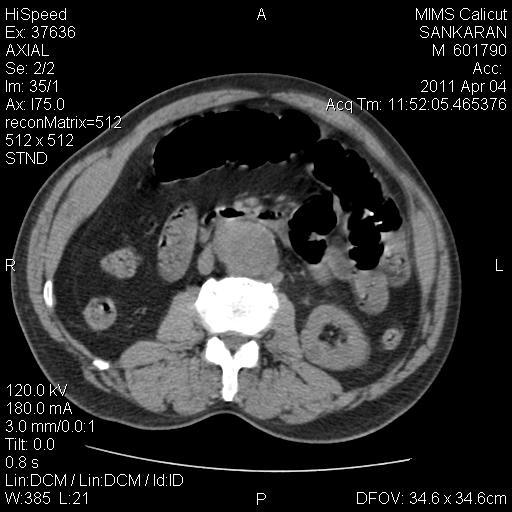

CT Image

Abdominal aortic aneurysm with maximum width of 4.8cm starting approximately at the level of left renal artery upto bifurcation

Abdominal USG showed abdominal aortic aneurysm of width 4.2cms with intraluminal thrombus with multiple renal calculi.

Patient was planned to obtain a CECT Abdomen but owing to the deranged renal parameters, it was deferred. Plain CT abdomen was hence taken which showed AAA and multiple renal calculi.Patient was planned for emergency laparotomy. It showed extensive small bowel gangrene extending from the DJ flexure upto the mid transverse colon. Mesenteric pulsations were absent and purulent foul smelling fluid in peritoneal cavity. Findings were discussed with the relatives and poor prognosis explained and the procedure abandoned. The post op period was critical as he was on a ventilator and his vitals started to deteriorate within hours of surgery. Eventually the patient expired.